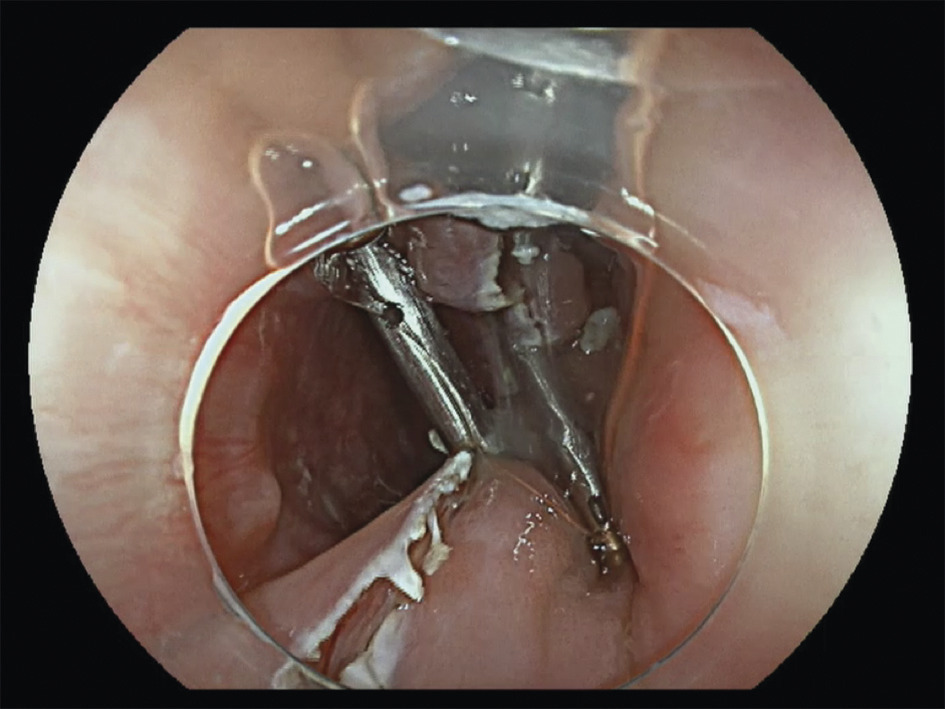

Le traitement endoscopique (fig. 2 à 5 ), ou myotomie transmuqueuse du cricopharyngien, peut être pratiqué par les ORL avec un diverticuloscope rigide ou par les gastro-entérologues experts, par endoscopie souple.2 Le diverticuloscope rigide impose une hyperextension cervicale parfois limitante. La diverticulotomie endoscopique consiste en une section de la paroi séparant le diverticule et l’œsophage, comprenant le muscle cricopharyngien, jusqu’à 5 mm du fond du diverticule. Elle offre des avantages par rapport à la chirurgie classique en termes de durée de procédure (< 1 heure) et d’hospitalisation. La réalimentation est plus précoce.

Taux médian de complication : 6 % par endoscopie souple. Ces techniques sont à préférer à la chirurgie chez les patients plus âgés et fragiles, malgré des récidives un peu plus nombreuses.